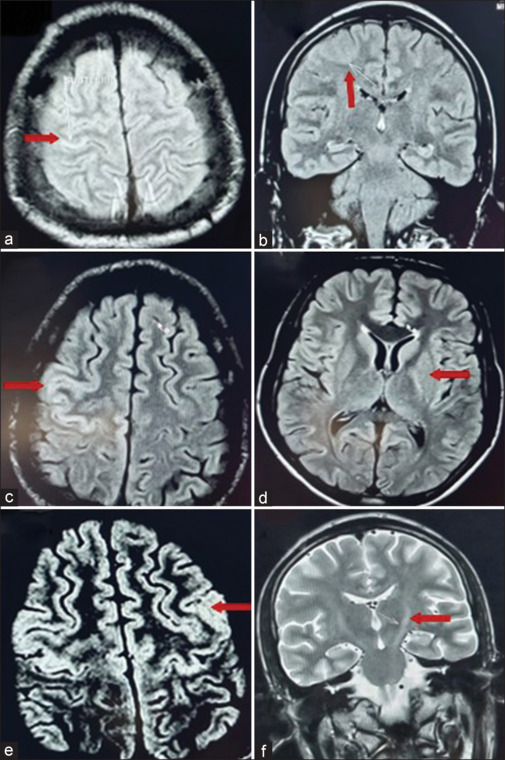

A young male with no known addictions and comorbidities presenting with recurrent clonic-myoclonic movements, initially localized to the left corner of the mouth and left upper limb, evolving into epilepsia partialis continua, despite appropriate sequential antiepileptic medications, subsequently progressed to refractory status epilepticus. He was tested positive for HIV infection and his neuroimaging revealed nonenhancing lesions, a novel finding in HIV-related encephalitis. We managed him with intravenous immunoglobulin along with multiple antiepileptic medications and highly active antiretroviral therapy (ART), and he exhibited a rapid clinical recovery over 3 weeks. This case highlights the importance of initiating immunomodulatory therapy promptly at presentation and underscores the challenges of managing drug interactions between antiepileptic drugs and antiretroviral therapy (ART), emphasizing the need for careful selection of medications in HIV-infected individuals.